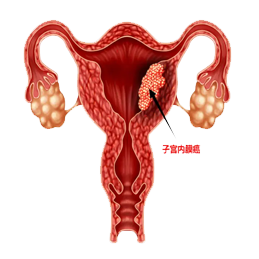

Ή”Ι§Α© «÷ΗΖΔ…ζ‘ΎΉ”Ι§ΒΡΕώ–‘÷ΉΝωΘ§Ήν≥ΘΦϊΒΡ «Ή”Ι§ΡΎΡΛΑ©Θ®Endometrial carcinomaΘ©Θ§ΥϋΤπ‘¥”ΎΉ”Ι§ΡΎΡΛΒΡœΗΑϊΓΘΉ”Ι§Α©Ω…“‘”ΑœλΉ”Ι§ΒΡ≤ΜΆ§≤ΩΖ÷Θ§Αϋά®Ή”Ι§ΧεΘ®Ή”Ι§…œ≤ΩΘ©ΚΆΉ”Ι§Ψ±Θ®Ή”Ι§œ¬≤ΩΘ©ΓΘΉ”Ι§ΧεΑ© «Ήν≥ΘΦϊΒΡάύ–ΆΘ§’ΦΥυ”–Ή”Ι§Α©≤ΓάΐΒΡ‘Φ90%ΓΘ‘ΎΡ≥–©«ιΩωœ¬Θ§Ή”Ι§Α©ΒΡ‘γΤΎΩ…ΡήΟΜ”–Οςœ‘÷ΔΉ¥Θ§“ρ¥ΥΥϋ≥Θ≥Θ‘ΎΧεΦλΜρΦλ≤ι÷–ΖΔœ÷ΓΘ